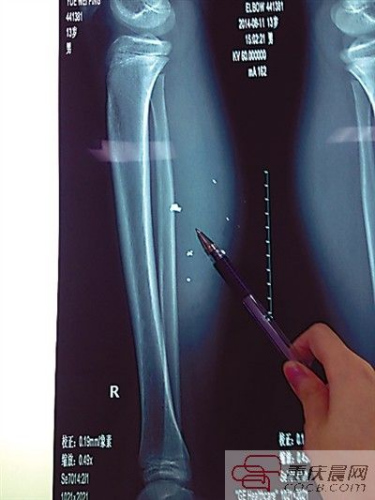

平平的小腿內異物清晰可見。

第二天,傷勢過重的平平轉院至兒童醫(yī)院,骨科醫(yī)生周悅航說,經檢查,平平右小腿腫脹明顯,發(fā)現有爆炸傷伴異物殘留,后側可見兩處1厘米裂口,傷口較深,約1.5-2厘米。通過X光片可見患兒右小腿皮下多處高密度影,即手機爆炸后進入小腿的異物,大約10處,需通過手術取出。